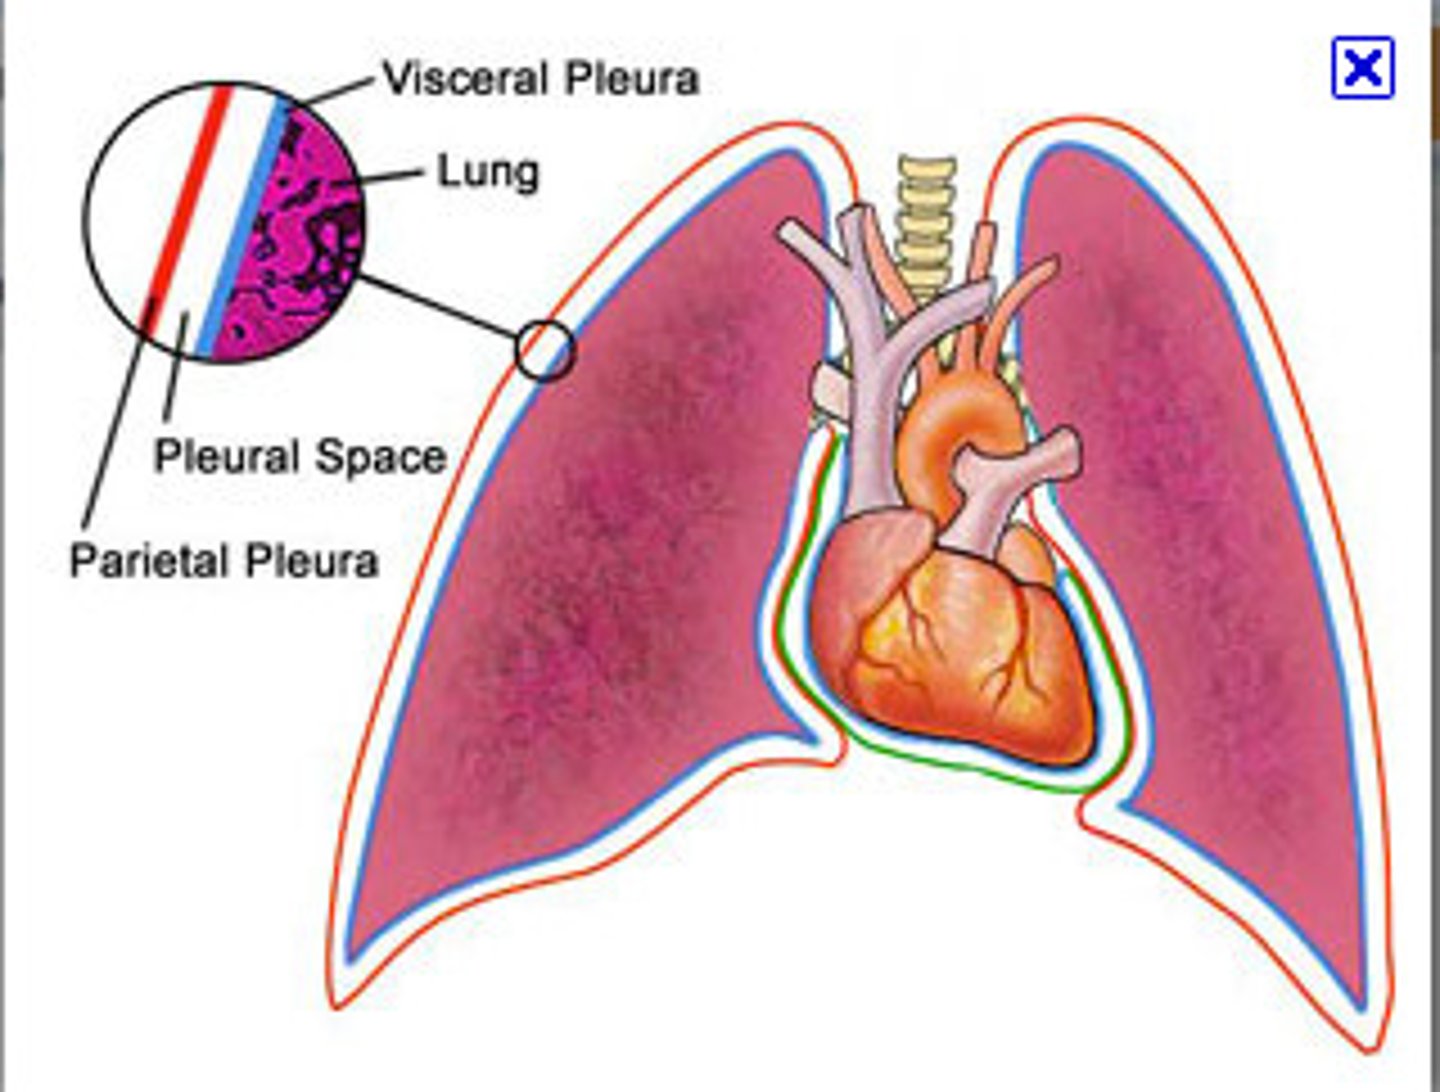

pleurae

thin, double-layered serosal membrane that divides thoracic cavity into two pleural compartments and mediastinum

parietal pleura

outermost layer of the pleura that connects to the thoracic wall, mediastinum, and diaphragm

visceral pleura

innermost layer of the pleura that is superficial to the lungs and extends into the lung fissures

pleural cavity

space between the visceral and parietal pleurae

pleural fluid

substance that acts as a lubricant for the visceral and parietal layers of the pleura during the movement of breathing